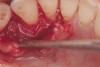

The patient had been referred for an implant consultation for the mandibular right canine. She had very deep probing depths on the lingual. When the flap was raised, a significant amount of subgingival calculus was seen as a local risk factor (Figure 18). However, she had no significant pathology to remove from the situation. Debridement was performed the same as in Case 3 with the rotary ultrasonic and manual instrumentation.

The defect was obturated with mineralized freeze-dried bone and hydrated with platelet-derived growth factor. As with any growth factor, when implementing it clinically, all growth factors require a carrier to bring that growth factor to the desired site, which do not elicit an inflammatory response. In this situation, it is the mineralized freeze-dried bone allograft. This combination was demonstrated by Rosen et al8 to be efficacious in treating intrabony defects. A biologic approach was taken both in terms of the graft and membrane (Figure 19). Primary closure was achieved.

Subgingival calculus and severe bone loss.

Figure 18

An amnion-chorion membrane adapted over the bone graft.

Figure 19